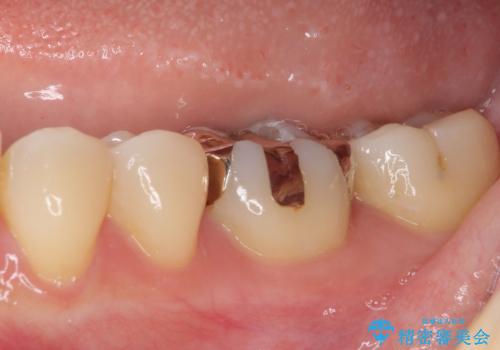

- 下の奥歯(右下7・左下7)にあって目立ってしまう銀歯を白くしたいとのことで来院された患者様です。

セラミックインレーにて修復治療を行うこととしました。